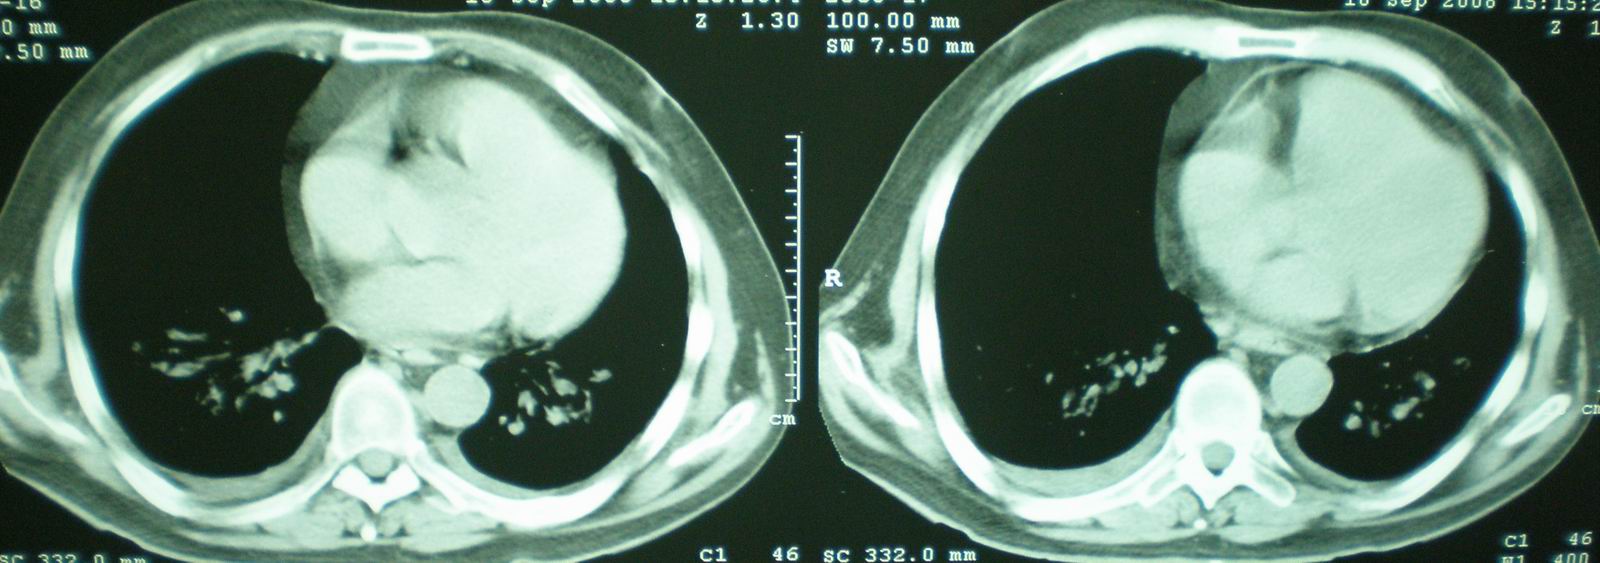

病人资料:男,52岁,因体癣股癣等皮肤病行激素治疗,因突然大剂量减药而起病,病情危急,9月8日曾在上级医院住院治疗,9月18日复查了ct片,相关检查及住院小结以图片资料上传。

[face=宋体]显然上级医院进行了抗结核,抗真菌,抗炎等治疗,目前病人肺内病灶基本消失,双侧胸腔积液,右侧积液量有吸收,抗结核一个多月,现在病人疑问,结核的诊断是否有疑义,抗结核是否继续,因为那个毕竟副作用大。[/face]

急性心衰所致肺水肿,双侧胸腔积液,少量心包积液可能?结合临床及其它检查.

我仔细看了下病人的出院小结,当时情况危急,诊断里有1型呼衰。心包周围的是脂肪密度。结合三次ct扫描的图象分析,个人认为:1、病人目前肺部病灶基本消失,双侧胸腔内少量积液,抗结核治疗才一个多月,就算是结核,抗结核治疗有效果,为何效果如此好,一点纤维灶的痕迹都没有呢,再就是患者做过气管镜检查及活检、痰检均未找到结核的证据。所以不支持结核的诊断。

2、结合现在的ct片,考虑:肺水肿及真菌感染,双侧胸腔积液。

急性呼吸窘迫综合征,肺水肿,与激素减量太快有关.双侧胸腔积液.